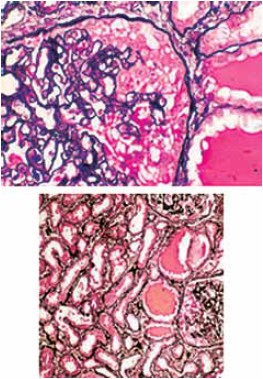

Assinale a alternativa que apresenta corretamente a doença na qual o acometimento renal apresenta microcistos tubulares, inflamação túbulo-intersticial e glomeruloesclerose extensa com aparente dilatação da cápsula de Bowman.

(Arquivo pessoal; imagens usadas com autorização.)